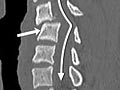

CT scan of the spine

Normal:

- Spinal bones (vertebrae) are normal in shape, number, and alignment.

- The discs and joints that support the spine are normal.

- The spinal canal is normal in size and shape.

- If contrast material is used, it flows evenly through the spinal canal. No narrowing or blockage of the spinal canal is present.

- None of the nerves leaving the spinal cord are compressed or pinched. No growths or bulges are present.

Abnormal:

- Spinal bones (vertebrae) are missing, damaged, or out of alignment.

- One or more discs may be damaged. One or more herniated discs are found.

- The flow of contrast material through the spinal canal is restricted or blocked, which may mean narrowing of the canal (spinal stenosis).

- The vertebrae show signs of arthritis or bone problems caused by osteoporosis.

- A condition that has been present from birth (congenital) is present in the spine or the vertebrae.

- An abscess or spinal tumor is found.